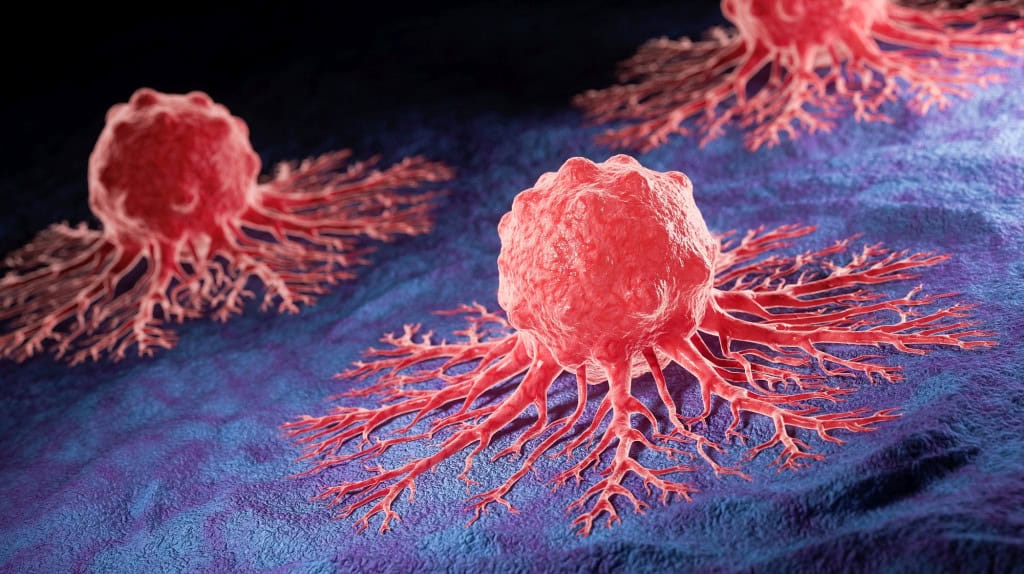

Ler maisResultados de pílula para câncer emocionam médicos em congresso de oncologia

Médicos e pesquisadores que estavam na sessão plenária da American Society of Clinical Oncology (ASCO) se levantaram qua...

Ler maisResultados de pílula para câncer emocionam médicos em congresso de oncologia

Médicos e pesquisadores que estavam na sessão plenária da American Society of Clinical Oncology (ASCO) se levantaram qua...